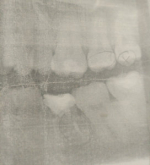

В начале этого года у меня начали прорезаться зубы мудрости. Не замечал появления их до появления дискомфорта, хотя небольшое смещение зубов было видно уже относительно давно. Зуб мешает и смещает зубной ряд. В бюджетной стоматологи отказались удалять, так как зуб здоровый. Что мне делать?

К сожалению, для полноценного прорезывания восьмого зуба места в зубном ряду недостаточно. Как правильно в этом случае зубы на пути прорезывания вызывают дискомфорт и скученность во фронтальном отделе. Рекомендуем Вам сделать рентгеновский снимок, который называется ортопантомограмма и обратиться к стоматологу-хирургу, возможно в частную стоматологию.